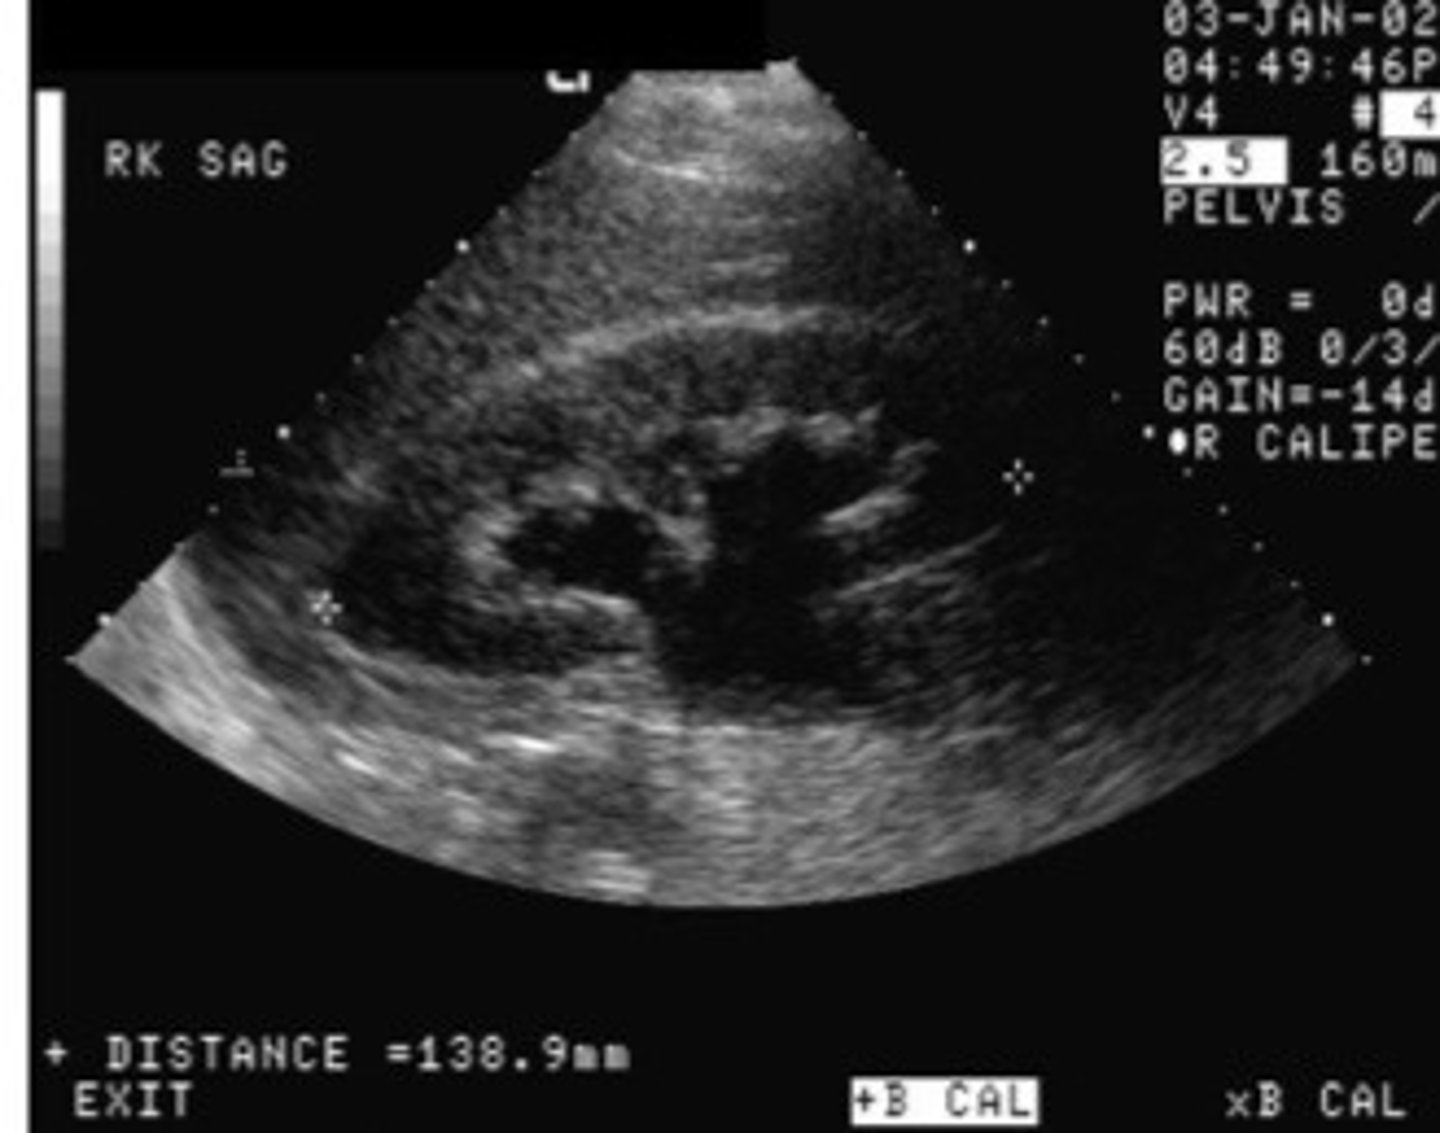

Nephrolithiasis

What does this image show

<p>What does this image show</p>